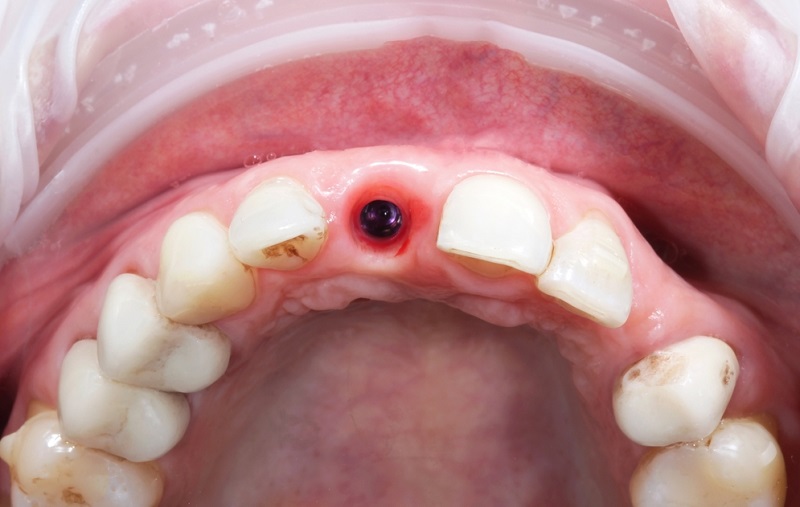

If the gum tissue around the implant begins to recede, exposing the implant and its metal post, could indicate implant failure.

7. Failure to integrate:

If your implant does not merge with your jawbone, it may become loose or fall out entirely.